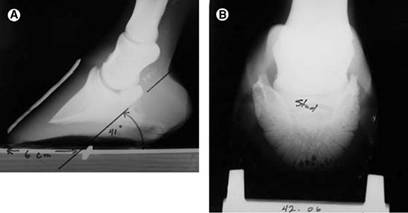

Palmarinio kampo dydis gali būti išmatuotas dviem būdais: kanopos kapsulės-žemės ir žemės atžvilgiu. Pirmasis metodas mažiau rodo pasagos sukeltą mechaninį poveikį, o daugiau informuoja apie minkštųjų audinių vientisumą kulno srityje, ypač pirštų pagalvėlėje. Antrasis būdas rodo pasagos mechaninį poveikį kanopai.

Daugumos sveikų pėdų su stipriu kulnu ir tvirtomis pirštų pagalvėlėmis, palmarinis kampas yra teigiamas. Tai reiškia, kad trečiojo pirštakaulio sparnai yra aukštesni nei viršūnė (4b pav.).

Kampo dydis taip pat priklauso nuo arklio veislės. Veislių, kurioms būdingos statesnės kanopos, palmarinis kampas yra didesnis. Kaustymas taip pat įtakoja palmarinio kampo dydį, į tai turi būti atkreiptas dėmesys atliekant matavimus (Redden R.F., 2003).

Didelis palmarinis kampas (lyginant su tai veislei būdingu palmarinio kampo dydžiu) gali būti laminito ar kitų patologijų atveju. Neigiamas palmarinis kampas rodo, jog trečiojo pirštakaulio sparnai yra žemiau nei jos viršūnė bei rodo minkštųjų audinių vientisumo pažeidimą kulno srityje (Redden R.F., 2003).

4 pav. a) Neigiamas 6º palmarinis kampas. b) Matoma rago-lapelių zona bei teigiamas 6º palmarinis kampas (Redden R.F., 2003)